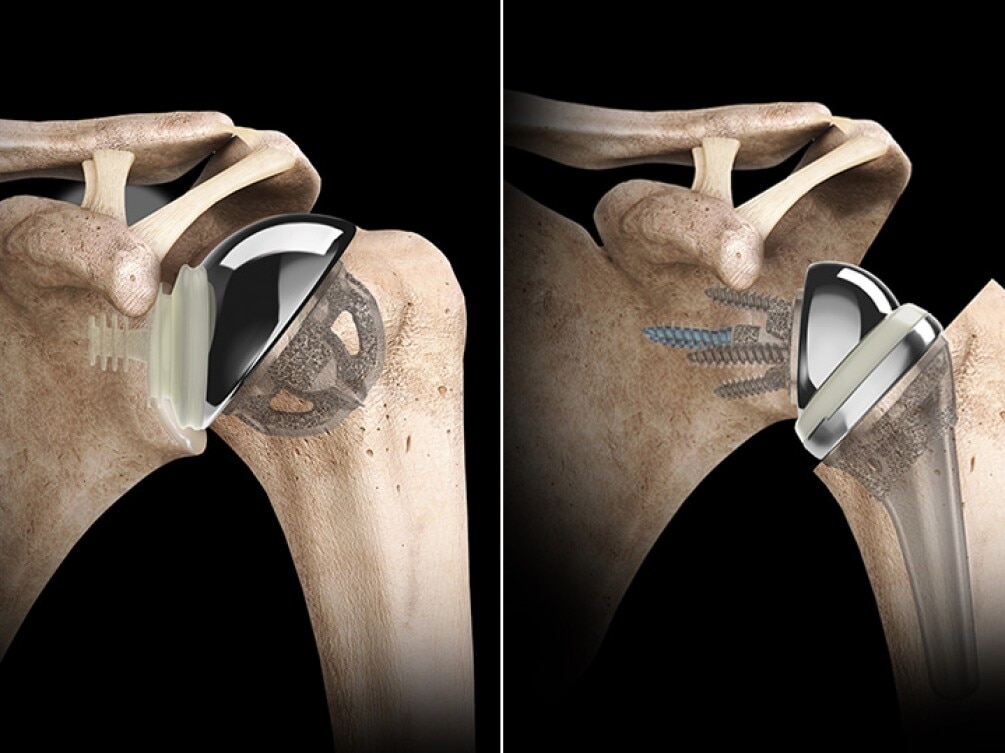

Shoulder Arthroplasty

Shoulder arthroplasty is a surgical procedure used to replace damaged or arthritic parts of the shoulder joint with artificial components. It is typically recommended for patients with severe osteoarthritis, complex fractures, or rotator cuff-related joint degeneration that limits mobility and causes chronic pain. At Rapha Sports and Regenerative Orthopaedics, our surgeons offer advanced shoulder replacement options tailored to each patient’s condition, lifestyle, and functional goals. Types of Shoulder Arthroplasty: Total Shoulder Replacement (Anatomic): Replaces both the ball (humeral head) and socket (glenoid) with prosthetic components. Best suited for patients with intact rotator cuff muscles and primary osteoarthritis. Reverse Shoulder Replacement: Reverses the normal anatomy of the shoulder by placing the ball component on the shoulder blade and the socket on the upper arm. Ideal for patients with rotator cuff tears, cuff tear arthropathy, or complex fractures. Hemiarthroplasty: Replaces only the ball portion of the joint. Often used in certain fractures or where the socket remains healthy. Partial/Stemless Shoulder Replacement: A bone-preserving option for select patients with less extensive damage, offering quicker recovery and less invasive techniques. Our multidisciplinary team ensures seamless care—from pre-operative planning to post-operative physiotherapy—focused on restoring function, reducing pain, and supporting long-term joint health.